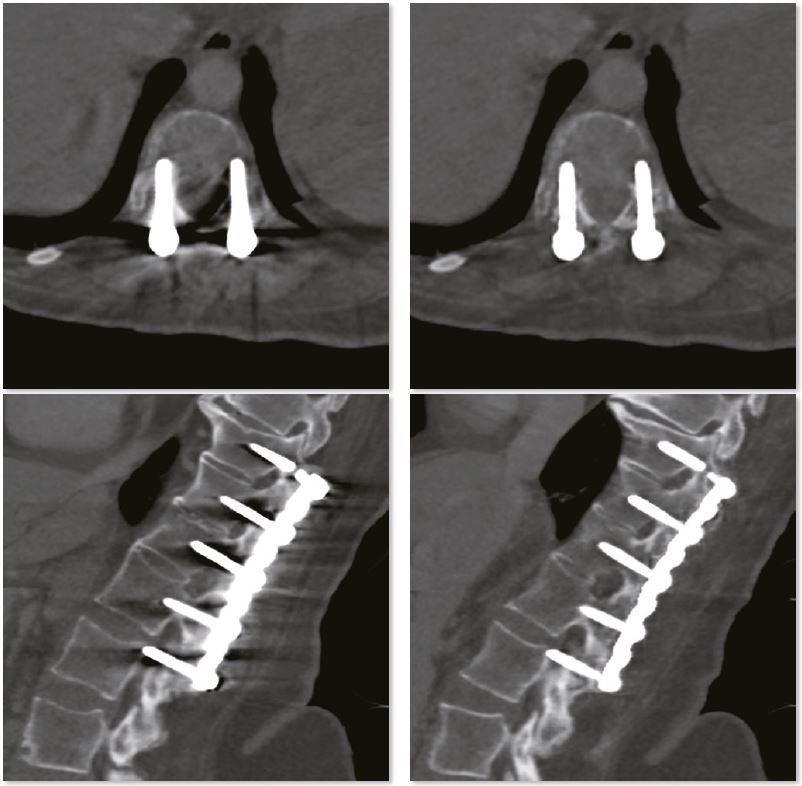

Для стабілізації заднього відділу хребта та збереження хребетного каналу використовується внутрішня фіксація. Зображення SEMAR забезпечують чудову деталізацію хребетного каналу без артефактів. Міжхребцеві дискові простори звужені та дегенеративні в цій частині поперекового відділу хребта

Фіксація поперекового відділу хребта

Для стабілізації заднього відділу хребта та збереження хребетного каналу використовується внутрішня фіксація. Зображення SEMAR забезпечують чудову деталізацію хребетного каналу без артефактів. Міжхребцеві дискові простори звужені та дегенеративні в цій частині поперекового відділу хребта.

Звичайне зображення

Зображення з SEMAR